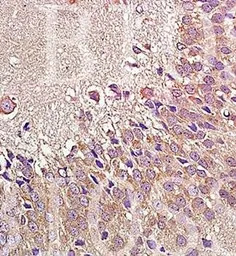

IHC-P analysis of rat brain tissue using GTX37593 NPY1R antibody.